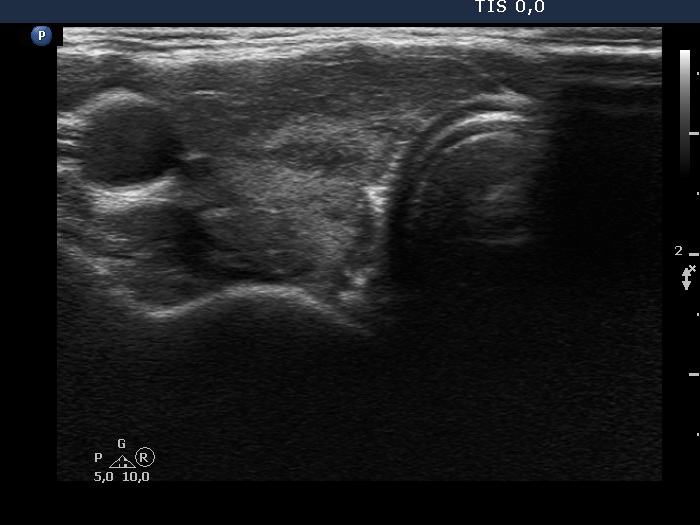

Right lobe, longitudinal scan

This is the usual course of Graves' disease regarding the change in echo pattern - before, during and after the activity of the autoimmune process. The only exception is the change in the size of the thyroid. In most cases, the thyroid increases during the activity of the disease, then returns to normal. However, in this patient the age counts: at the first examination, the patient was only 15-year-old.